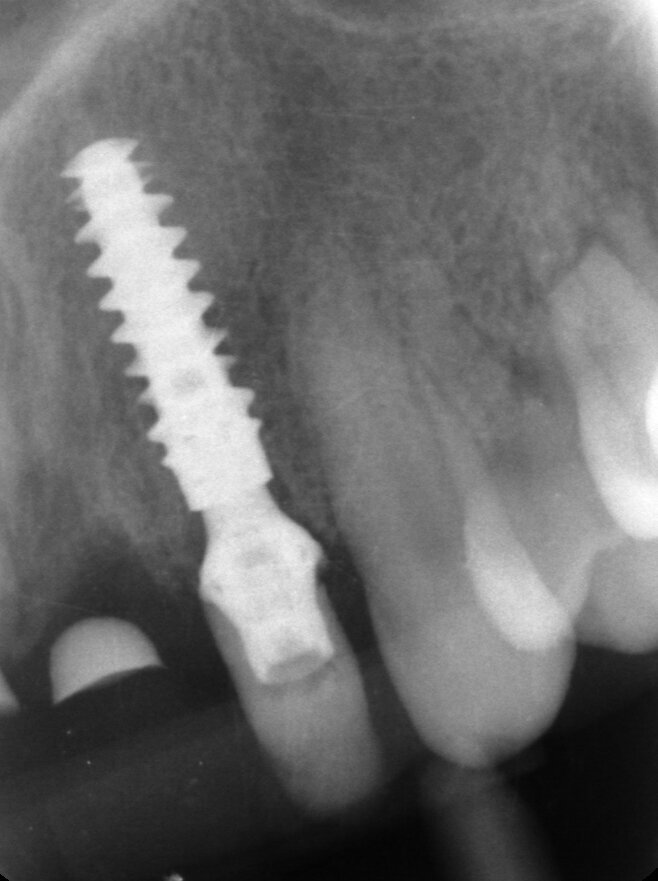

Il piano di trattamento prevede l’estrazione degli elementi dentali, l’inserimento di due impianti e la realizzazione di una protesi fissa di quattro elementi. Il problema da gestire è quello della fase provvisoria. Non è ipotizzabile una protesi mobile e quindi programmiamo di inserire subito dopo l’intervento un provvisorio immediato. Questo ci consente di condizionare da subito i tessuti periimplantari e anche le zone dei ponti. Si rileva un’impronta digitale (Figg. 5, 6), e la programmazione degli impianti viene effettuata con un software di chirurgia guidata (Fig. 7) e la posizione degli impianti nello spazio biologico e nello spazio protesico viene fatta sulla base di una ceratura diagnostica (Figg. 8, 9). Inseriamo gli impianti virtuali nell’osso disponibile (Figg. 10-13) e in relazione all’aspetto protesico correggiamo l’asse di inclinazione degli impianti con componenti secondarie angolate a 17° (Figg. 14, 15). Questo ci consentirà di realizzare una protesi avvitata con i fori situati nella zona palatale.

Il nostro obiettivo è quello di riuscire a dare alla paziente un provvisorio immediato nell’arco di due ore. Questo diventa possibile perché abbiamo utilizzato un flusso digitale fin dall’inizio. In laboratorio vengono realizzate la dima chirurgica (Figg. 16, 17), la dima protesica (Fig. 18) e anche il provvisorio (Figg. 19-21) che contiene delle alette di riposizionamento. Il tutto gestito con modelli digitali sui quali saremo in grado di funzionalizzare il provvisorio post-chirurgico (tecnica DIL). In un caso come questo se utilizziamo un flusso digitale possiamo evitare subito dopo la chirurgia di rilevare un’impronta degli impianti inseriti. Infatti, utilizziamo una dima chirurgica che ci faciliterà le fasi di intervento. La dima ci consentirà di non fare lembi e nessuna incisione di rilascio (Fig. 22), dopo aver inserito gli impianti (BLX Straumann) (Figg. 23-31) e aver controllato il loro alloggiamento, inseriamo sugli stessi dei transfert da impronta (Fig. 32).

Fig. 26 - Impianto BLX Straumann.

Fig. 27 - Posizionamento impianto 1.2.

Fig. 28 - Alloggiamento finale.

Fig. 29 - Posizionamento impianto 2.2.

Fig. 30 - Alloggiamento finale.